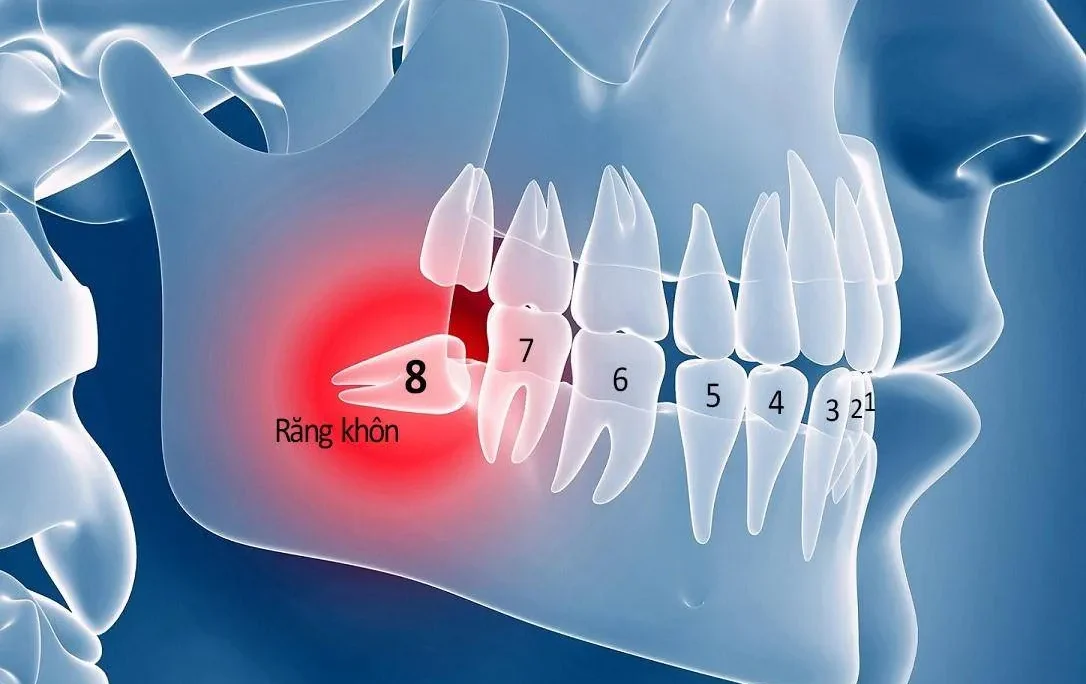

- Thay đổi cấu trúc giải phẫu: Xương tiêu khiến xoang hàm trên bị giãn rộng (pneumatization) và ống thần kinh hàm dưới lộ gần bề mặt, làm tăng nguy cơ tổn thương các cấu trúc quan trọng này trong quá trình phẫu thuật.

- Thiếu hụt Xương nghiêm trọng: Chiều cao xương còn lại ở hàm trên dưới 5mm hoặc xương hàm dưới sát ống thần kinh, hoặc chiều rộng xương quá mỏng (dưới 4mm).

- Cần can thiệp cấu trúc lân cận: Yêu cầu các thủ thuật như chuyển vị tạm thời bó mạch thần kinh hoặc phẫu thuật tạo hình mô mềm lớn.